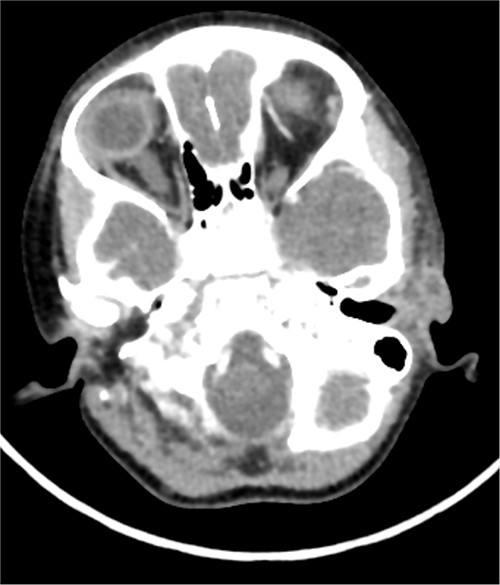

A CT scan showed a left-sided infected cystic lesion that is consistent with the preauricular sinus but did not show any cysts or tracts of the branchial cleft cyst (Fig. 5). Renal ultrasound showed normal findings and play audiogram showed normal hearing level. The patient consented for direct laryngobronchoscopy with excision of the branchial fistula, as well as preauricular sinuses excision and tonsillectomy.

This is the axial cut CT that showed left-sided cystic lesion representing infected preauricular sinus. The CT did not show the second branchial cyst or tract that was found in clinical examination.